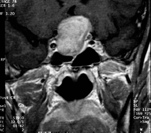

Der transsphenoidale Zugang über die Nase und Keilbeinhöhle führt zur Schädelbasis, in der Mitte zum Sellaboden mit der darüber gelegenen Hypophyse und hinten zum Clivus. Besonders geeignet ist er für Hypophysenadenome (siehe MRT Bild) und Clivuschordome im frühen Stadium. Dieser Zugang wird hier sowohl mikroskopisch als auch endoskopisch durchgeführt.

Hypophysentumore (siehe MRT) verlagern die Sehnervenkreuzung nach oben und führen zu bitemporalen Gesichtsfelddefekten und Sehminderung auf beiden Augen. Mit Ausnahme der Prolactinome, die primär medikamentös behandelt werden, wäre der transsphenoidale Zugang der Zugang der ersten Wahl.

Hypophysenadenom intra - / suprasellär. Großer suprasellärer Anteil ( = oberhalb der Sella turcica ) mit nachfolgend Anhebung und massiver Kompression des Chiasma opticum ( = Sehnervenkreuzung ). Unbehandelt droht dem Patienten die vollständige Erblindung, die Operation "durch die Nase" ist heute ein risikoarmes Verfahren, welches gute Ergebnisse erbingt.